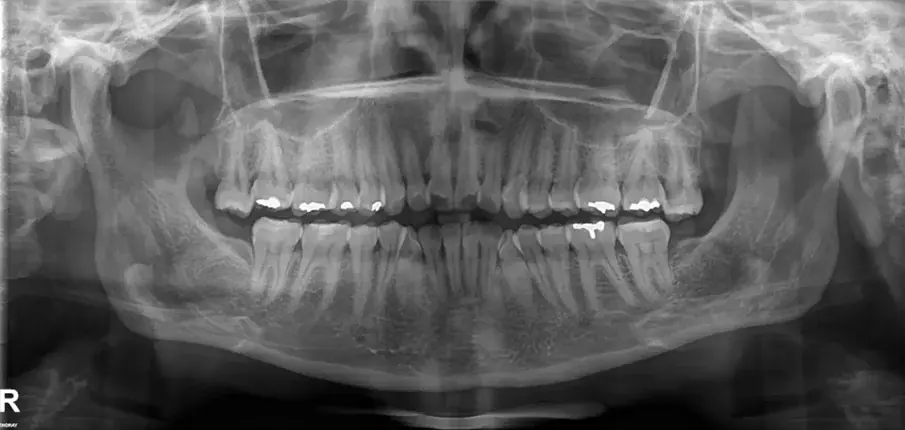

Първоначална цефалометрична рентгенография и панорамна дентална томография.